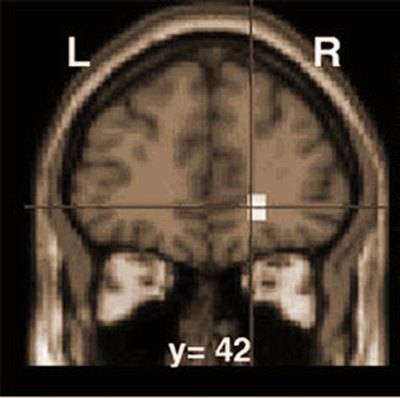

وقام هذا الفريق باستخدام آلية لتصوير المخ تعرف باسم التصوير الوظيفي بالرنين المغناطيسي. ورصد الباحثون نشاط المخ حيث وجد أن الإطراء من الغرباء له نفس الأثر الذي يحدثه المال من حيث تنشيط مركز المكافأة في المخ حيث يشبع المديح عند الإنسان "الحاجة إلى الانتماء". وقال ساداتو إن نتيجة الدراسة تعد خطوة أولى نحو تفسير السلوكيات الاجتماعية البشرية المعقدة مثل إيثار الغير.

التصوير الوظيفي بالرنين المغنطيسي هو تقنية جديدة ورائعة، وحبذا لو استغل علماء المسلمين هذه التقنية في إجراء أبحاث علمية جديدة، فلدينا في القرآن والسنة الكثير من الأفكار مثل تأثير الزكاة وتأثير الصلاة والصيام وحسن الخلق وغير ذلك على أداء الدماغ. وهذا الجهاز ويرمز له اختصاراً fMRI يقيس درجة نشاط المخ من خلال تدفق الدم فيه، وكما نعلم يحوي الدم نسبة من الأكسجين، وبالتالي هذه الذرات من الأكسجين لديها نشاط كهربائي يستطيع جهاز fMRI التقاط وقياس هذا النشاط، وبالتالي معرفة المنطقة النشطة في المخ أثناء القيام بعمل ما.